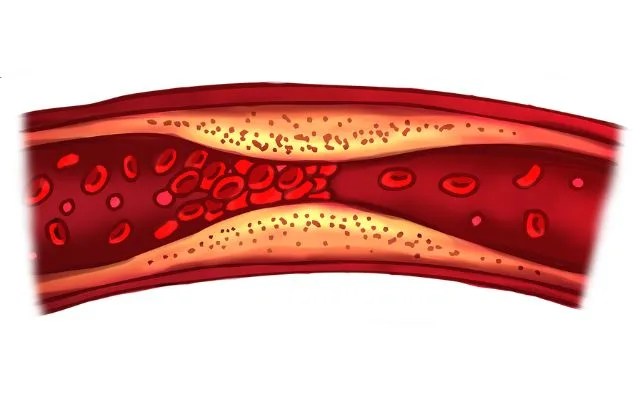

¿Qué es una arritmia cardíaca?

Una arritmia es una alteración en el ritmo normal de los latidos del corazón, que puede ser demasiado rápido (taquicardia), lento (bradicardia) o irregular. Si bien algunas son benignas y no necesitan tratamiento, otras pueden ser graves y requerir atención especializada para controlar los riesgos.